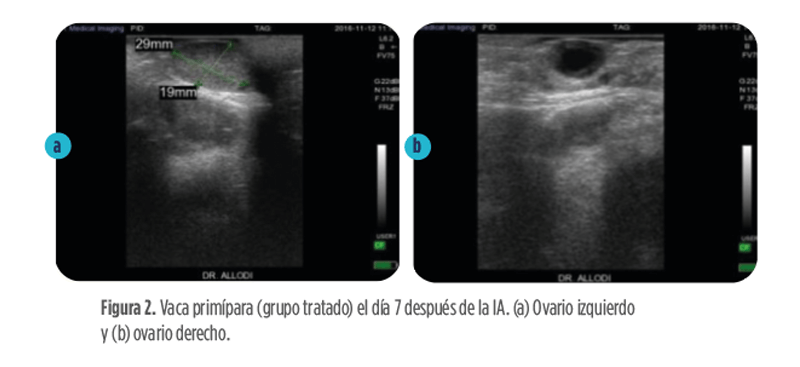

En un estudio de campo en Italia (Allodi et al.; no publicado), se evaluó el efecto de la administración de 2500 UI de hCG (Calier) en la formación de uno o más cuerpos lúteos accesorios (CL) y la posible mejora de la tasa de concepción (TC) en el grupo tratado.

Cincuenta vacas primíparas (grupo tratado) con 2500 UI de hCG (Calier) por inyección intramuscular el día 7 después de la IA.

Cincuenta vacas primíparas (grupo control) recibieron placebo (los mismos ml que el grupo tratado en este caso de NaCl al 0,9 %).

El día 7 después de la IA. un subgrupo de 20 animales por grupo se sometió a una ecografía para evaluar la presencia y el volumen de los CL.

El día 14 post-IA, los mismos animales fueron reevaluados mediante ecografía para comprobar la formación de uno o más CL accesorios y para calcular el nuevo volumen lúteo.